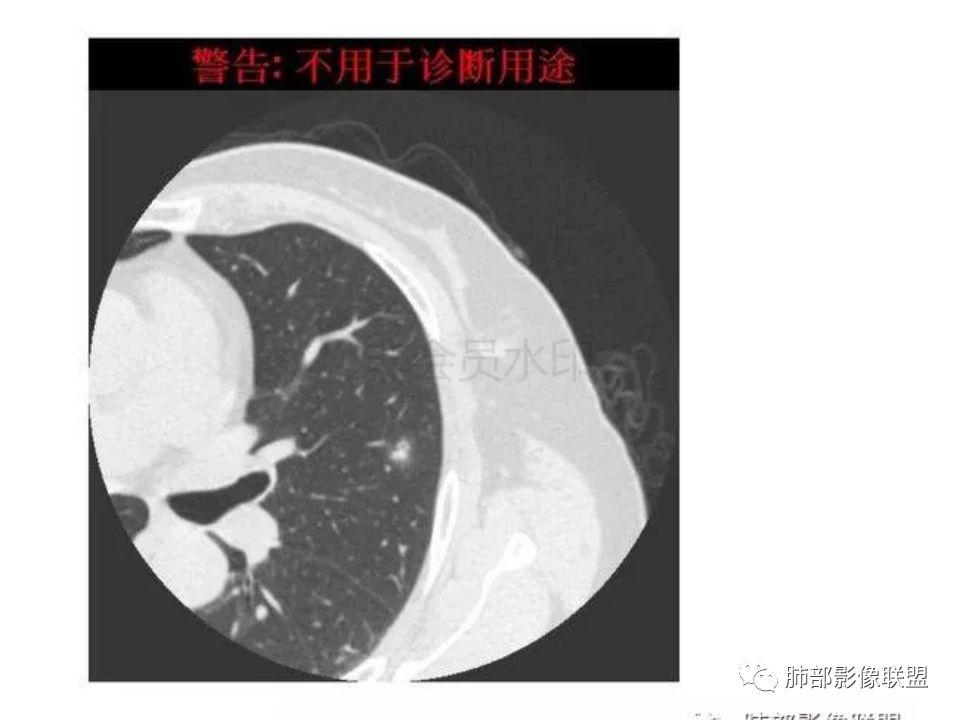

三生石上:支气管有截断,周围有晕,有空泡,腺癌?毛勤香:左肺下叶近胸膜下结节,周围磨玻璃影,边界似稍模糊,局部细支气管截断,实性区和磨玻璃区分界突然,隐约细毛刺,首先考虑感染性,隐球菌?待排腺癌MIA伴肺泡塌陷可能。常规治疗后复查。Coke with ice:IACM-Imaging :孤立胸膜下结节,其内见小泡,周围模糊的晕,晕中软毛刺,近端与血管相连,血管自然通过,气管进入结节内部一半,猜个隐球吧。第二腺癌,建议复查。田园晚风:考虑腺癌紫气东来:左肺上叶,磨玻璃实性毛刺,空泡,支气管截断,腺癌雪颜:左肺上叶结节状密度增高影,周围有晕,感觉周围模糊,有血管进入,里面有空泡征,隐约看到里面有支气管穿过,考虑炎性,隐球菌感染?腺癌待排THINKER:上叶尖后,SPN,有晕,软毛刺,无胸膜凹陷,分叶丶收缩不明显,支气管进入,远端阻塞,首选肉芽肿,PC或炎性结节,有一支血管滋养,鉴别腺癌,增殖性结核结节不支持期:左上肺结节周围有晕 晕中见细软毛刺 首先考虑隐球菌一米阳光:左肺上叶磨玻璃影,空泡,周围毛刺,月牙铲,支气管通过,周围有晕,考虑腺癌我的FY:毛刺,小空泡,磨玻璃考虑恶性崔少钢:小病灶,内有支气管,空泡征,实变不规则,放大了,感觉晕有点偏清,考虑恶性。小病灶里面有支气管是值得高度怀疑的。没有病史。彭君:左肺上叶舌段结节 周围晕模糊 内小支气管扩张 近端与血管相连 自然通过 首先考虑炎性 隐球菌?边缘月牙铲 腺癌待鉴别徐婕:左上肺结节周围有晕 ,晕中见细软毛刺 ,晕边界不太清,先考虑隐球菌张帅:左肺上叶尖后段实性病灶,以细支气管为中心,周围呈毛玻璃样影,并可见密集分布毛刺,内可见支气管征,支气管呈壁呈结节样改变,病灶周围可见血管增粗。考虑 淋巴瘤?鉴别隐球。张延军:混合型磨玻璃结节,伴毛刺,支气管截断,空泡,考虑浸润性腺癌,建议抗炎治疗后复查XGQ:支持隐球春秋:结节伴晕征,晕中毛刺,相邻小支气管近端进入,远端阻塞,近端血管相连,首先考虑隐球菌王秀仙:左肺上叶混合型磨玻璃结节,支气管截断,空泡,有毛刺,考虑浸润性腺癌,建议抗炎治疗后复查玫:左肺上叶磨玻璃结节影,薄扫见长短不一毛刺,有空泡,病灶边缘见晕征,考虑小腺癌可能,不除外炎性结节。zyf:左肺下叶近胸膜下结节,周围有晕,细软毛刺,有支气管进入,实性区和磨玻璃区分界明显,首先考虑感染性,隐球菌?查隐球菌荚膜抗原!RockJ-ason:考虑隐球采莲:左上肺靠近胸膜下实性结节影,边缘模糊,周围有晕及晕中毛刺,支气管进入通畅,有小空泡。考虑炎性病变,隐球可能性大。鉴别结核。Harvey:左肺下叶舌部小结节,边缘见磨玻璃影,边界欠清,内见支气管、管壁不光整,偏向恶性。鉴别隐球菌lmg:左肺上叶混合小结节,有晕,边界模糊,有有小毛刺。考虑炎性病变,隐球收选。AIS并肺泡塌陷带排。山河:倾向腺癌红日东升:GGO边界似清非清,内部好像不是小空泡,是小支气管腔,倾向炎性病变,常规抗炎复查除外腺癌,尤其粘液腺癌。

隐球菌感染孤立病灶与肺腺癌结节在影像上有时难分彼此,尽管隐球菌胸膜下更常见。

1.隐球菌病灶往往是实性密度结节为主伴周边边界不清楚的晕,有时可见晕内细软毛刺。

微浸润腺癌常常是磨玻璃密度为主的结节,边界比较清楚,并似乎有弧线形小叶间隔阻挡的痕迹。

实性结节的腺癌则很少有磨玻璃晕,往往会有粗短的硬毛刺。

2.隐球菌病灶形态往往圆钝柔和,缺乏收缩能力,很少出现腺癌的那种胸膜牵拉和棘状突起。

3.病灶内支气管安然无恙隐球菌病灶更加多见

4.隐球菌病灶增强扫描可轻度强化。既不同于结核灶的几乎不强化,也不同于肺腺癌的明显强化。

该患者实性成分为主,可惜未提供增强扫描图像。